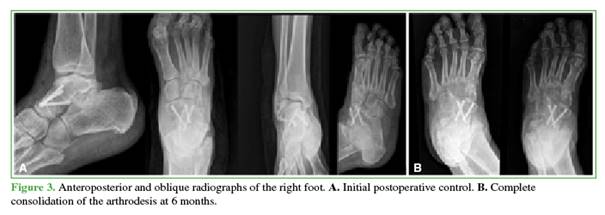

Postoperatively, control radiographs were obtained, analgesia was administered, and intravenous antibiotic prophylaxis was given for 24 hours. Early rehabilitation was indicated by the physiatry team.

The patient was discharged. At the 3-week follow-up visit, sutures were removed. Weight-bearing was restricted for 8 weeks, after which progressive loading was allowed.

At the conclusion of follow-up, 18 months postoperatively, the patient had a stable, plantigrade, pain-free foot.

The American Orthopaedic Foot and Ankle Society (AOFAS) score was 87.